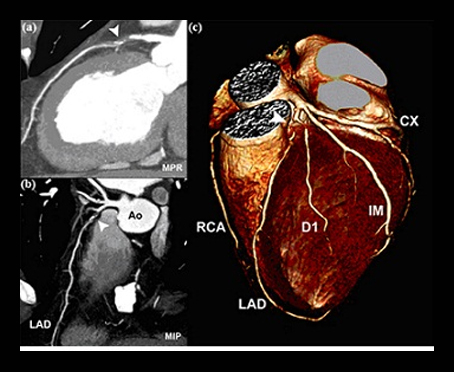

CT Coronary Angiography

By 128 Slice Dual Source Dual Energy CT Scanner

The ever evolving and dynamic advances in the field of Radiology have given birth to highly advanced technique in the form of 128 Slice CT scanner with manifold advantages over its immediate 64 Slice predecessor.Further, the dual source in the CT scan that makes a quantum difference in the quality and speed of imaging. Dual energy applications give insight into many areas that were outside the domain of CT scan.

• CT Coronary Angiography to evaluate suspected Coronary Artery Disease

• Rule Out Coronary plaques, calcification and Stenosis

• Evaluate Bypass Grafts & Coronary Stents

• Triple rule out for coronary, pulmonary and thoracic aorta pathologies

• Other angiographies such as carotid, cerebral, renal, thoracic aorta, abdominal aorta, portal circulation and peripheral arteries.

• Exquisite 3D images